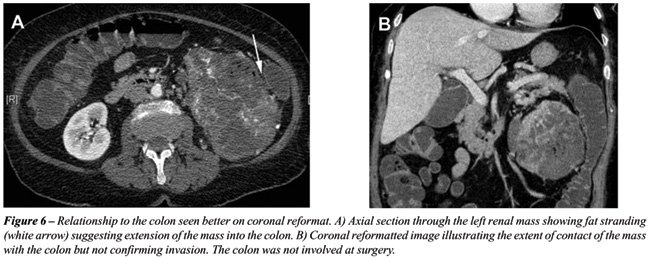

With the rapid acquisition of multiple simultaneous slices and thin-section reformatted coronal and/or sagittal images, the 64-slice CT scanner provides excellent detail in demonstrating local extension to the bowel and retroperitoneum (see Figures-2, 3, 5, 6 and 7). Multiplanar three-dimensional reconstruction techniques including volume rendering, maximum intensity projection and shaded surface display provide comprehensive information about the relationships and possible involvement of vascular structures in renal neoplasms.